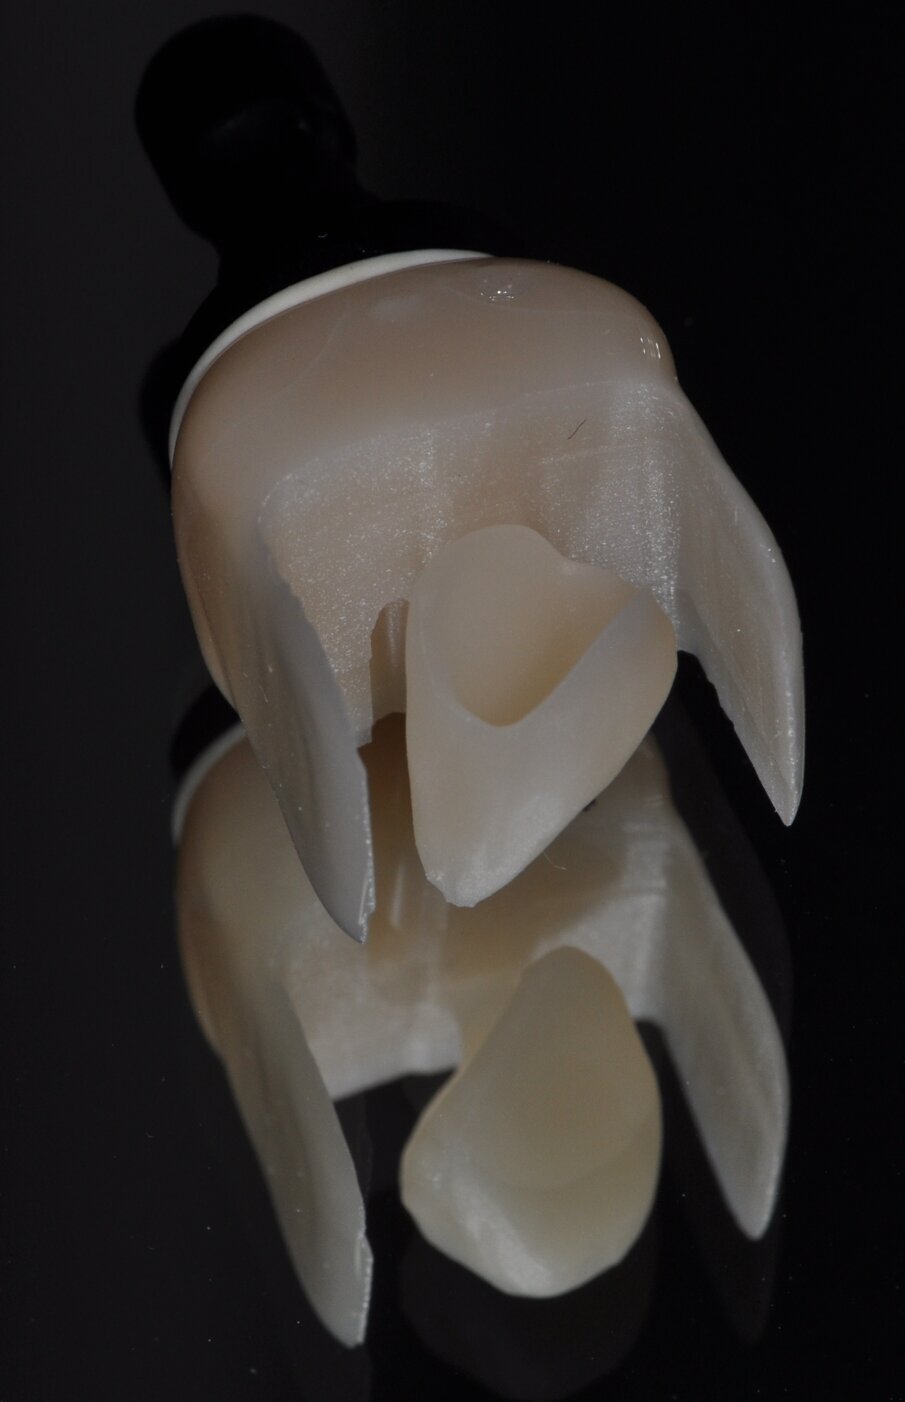

Fig. 11: Single crown milled from a ceramic block

The restorations were milled from blocks of a zirconia-reinforced lithium silicate (Celtra Duo; Dentsply Sirona Restorative) of A2 HT shade, finished with water-cooled diamond cutters and adapted on the model (Figs. 10 and 11).